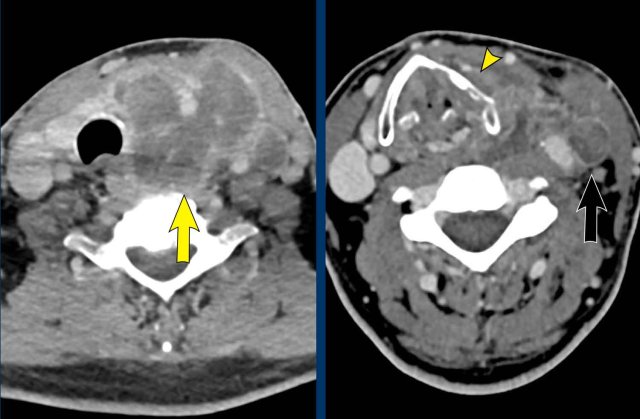

Images

CT of the head and neck shows an invasive thyroid mass with paralaryngeal and prevertebral extension and involvement of thyroid cartilage (yellow arrowhead).

There is a tumor thrombus in the jugular vein (black arrow).

Continue with the next images...

Notice the invasion of the thyroid cartilage (yellow arrowhead).

On the edge of the scan there was a brain metastasis.

Discusson

The Horner is caused by influencing the preganglionic system.

There are numerous fibers connecting the middle cervical ganglion (MCG) and inferior cervical ganglion (ICG), which are located anterior and posterior to the vertebral artery.

Final diagnosis

Anaplastic thyroid carcinoma.

This cancer is one of the most aggressive tumors and has a bad prognosis.